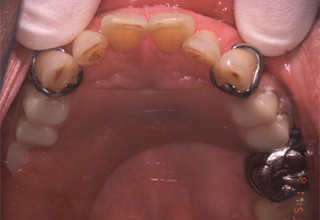

初診時の口腔内写真 主訴を考慮した保険の義歯

図1a

図1aは初診時に話しづらさと装着時の違和感を訴え来院した患者の義歯装着時の口腔内写真である. 図1bは、保険の義歯ではあるが、この主訴を考慮し装着した義歯である。

発音については舌の動きを阻害しないよう,また装着感については大連結子の形状や走行,義歯床縁の形態を配慮した。